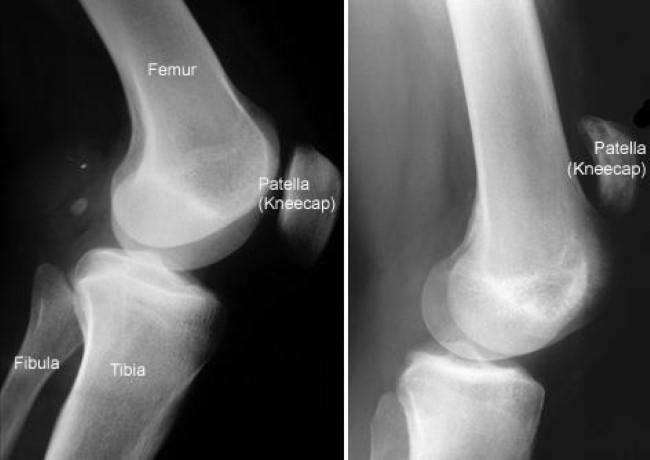

X-rays. The kneecap moves out of place when the patellar tendon tears. This is often very obvious on a side view X-ray of the knee. Complete tears can often be identified with these X-rays alone.

x-rays of normal knee and knee with torn patellar tendon

(Left) This X-ray taken from the side shows the normal location of the kneecap. (Right) This X-ray shows that the kneecap has moved out of place due to a torn patellar tendon.

Reproduced and adapted from J Bernstein, ed: Musculoskeletal Medicine. Rosemont, IL, American Academy of Orthopaedic Surgeons, 2003.